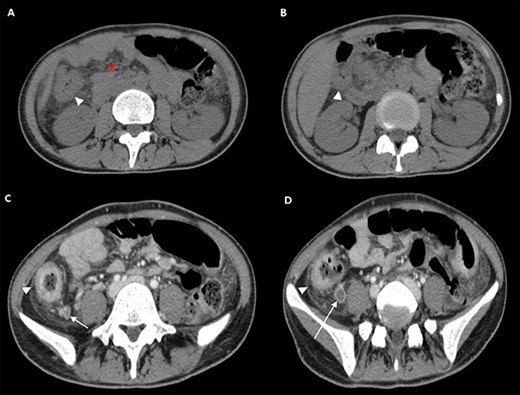

The following tests were carried out in ER: swab for severe acute respiratory syndrome coronavirus 2 (SARS-CoV2; negative), electrocardiogram, blood tests showing normocytic anemia, without leukocytosis, mild lymphocytopenia, and elevated C-reactive protein (CRP, 47 mg/L), chest X-ray (negative). Contrast-enhanced computed tomography (CT) showed increased densification of adipose tissue along the whole colon, the cecum and part of the ascendant had thickened walls (Fig. 1, panel A and B) with enhancement of the mucosa and submucosa edema, locoregional lymphoglandular large ~2 cm also partially colliquate (Fig. 1, panel C and D); lumen narrowing and strictures along the preterminal ileum and ascites. A colonscopy was performed, which revealed a patulous ileocecal valve, a bowel that was completely subverted from the cecum to the hepatic flexure with multiple and extensive deep fibrin-coated ulcers; the residual mucosa appeared pink with multiple pseudopolipoid protrusions (Fig. 2). Tests for HIV, HCV, stool cultures, parasitological and Clostridium difficile toxin were all negative and she was immune to hepatitis B virus. Quantiferon-test still outstanding.

CT scan of the Abdomen obtained at this presentation. Transverse CT images (Panel A and B), obtained before administration of intravenous contrast material, show increased densification of adipose tissue (asterisk) along the whole colon, the cecum and part of the ascendant, which had thickened walls (arrowheads). Transverse CT images (Panel C and D), obtained after administration of intravenous contrast material, show the mucosa enhancement and submucosa edema due to flogosis (arrowheads), locoregional lymphoglandular also partially colliquate (arrows).